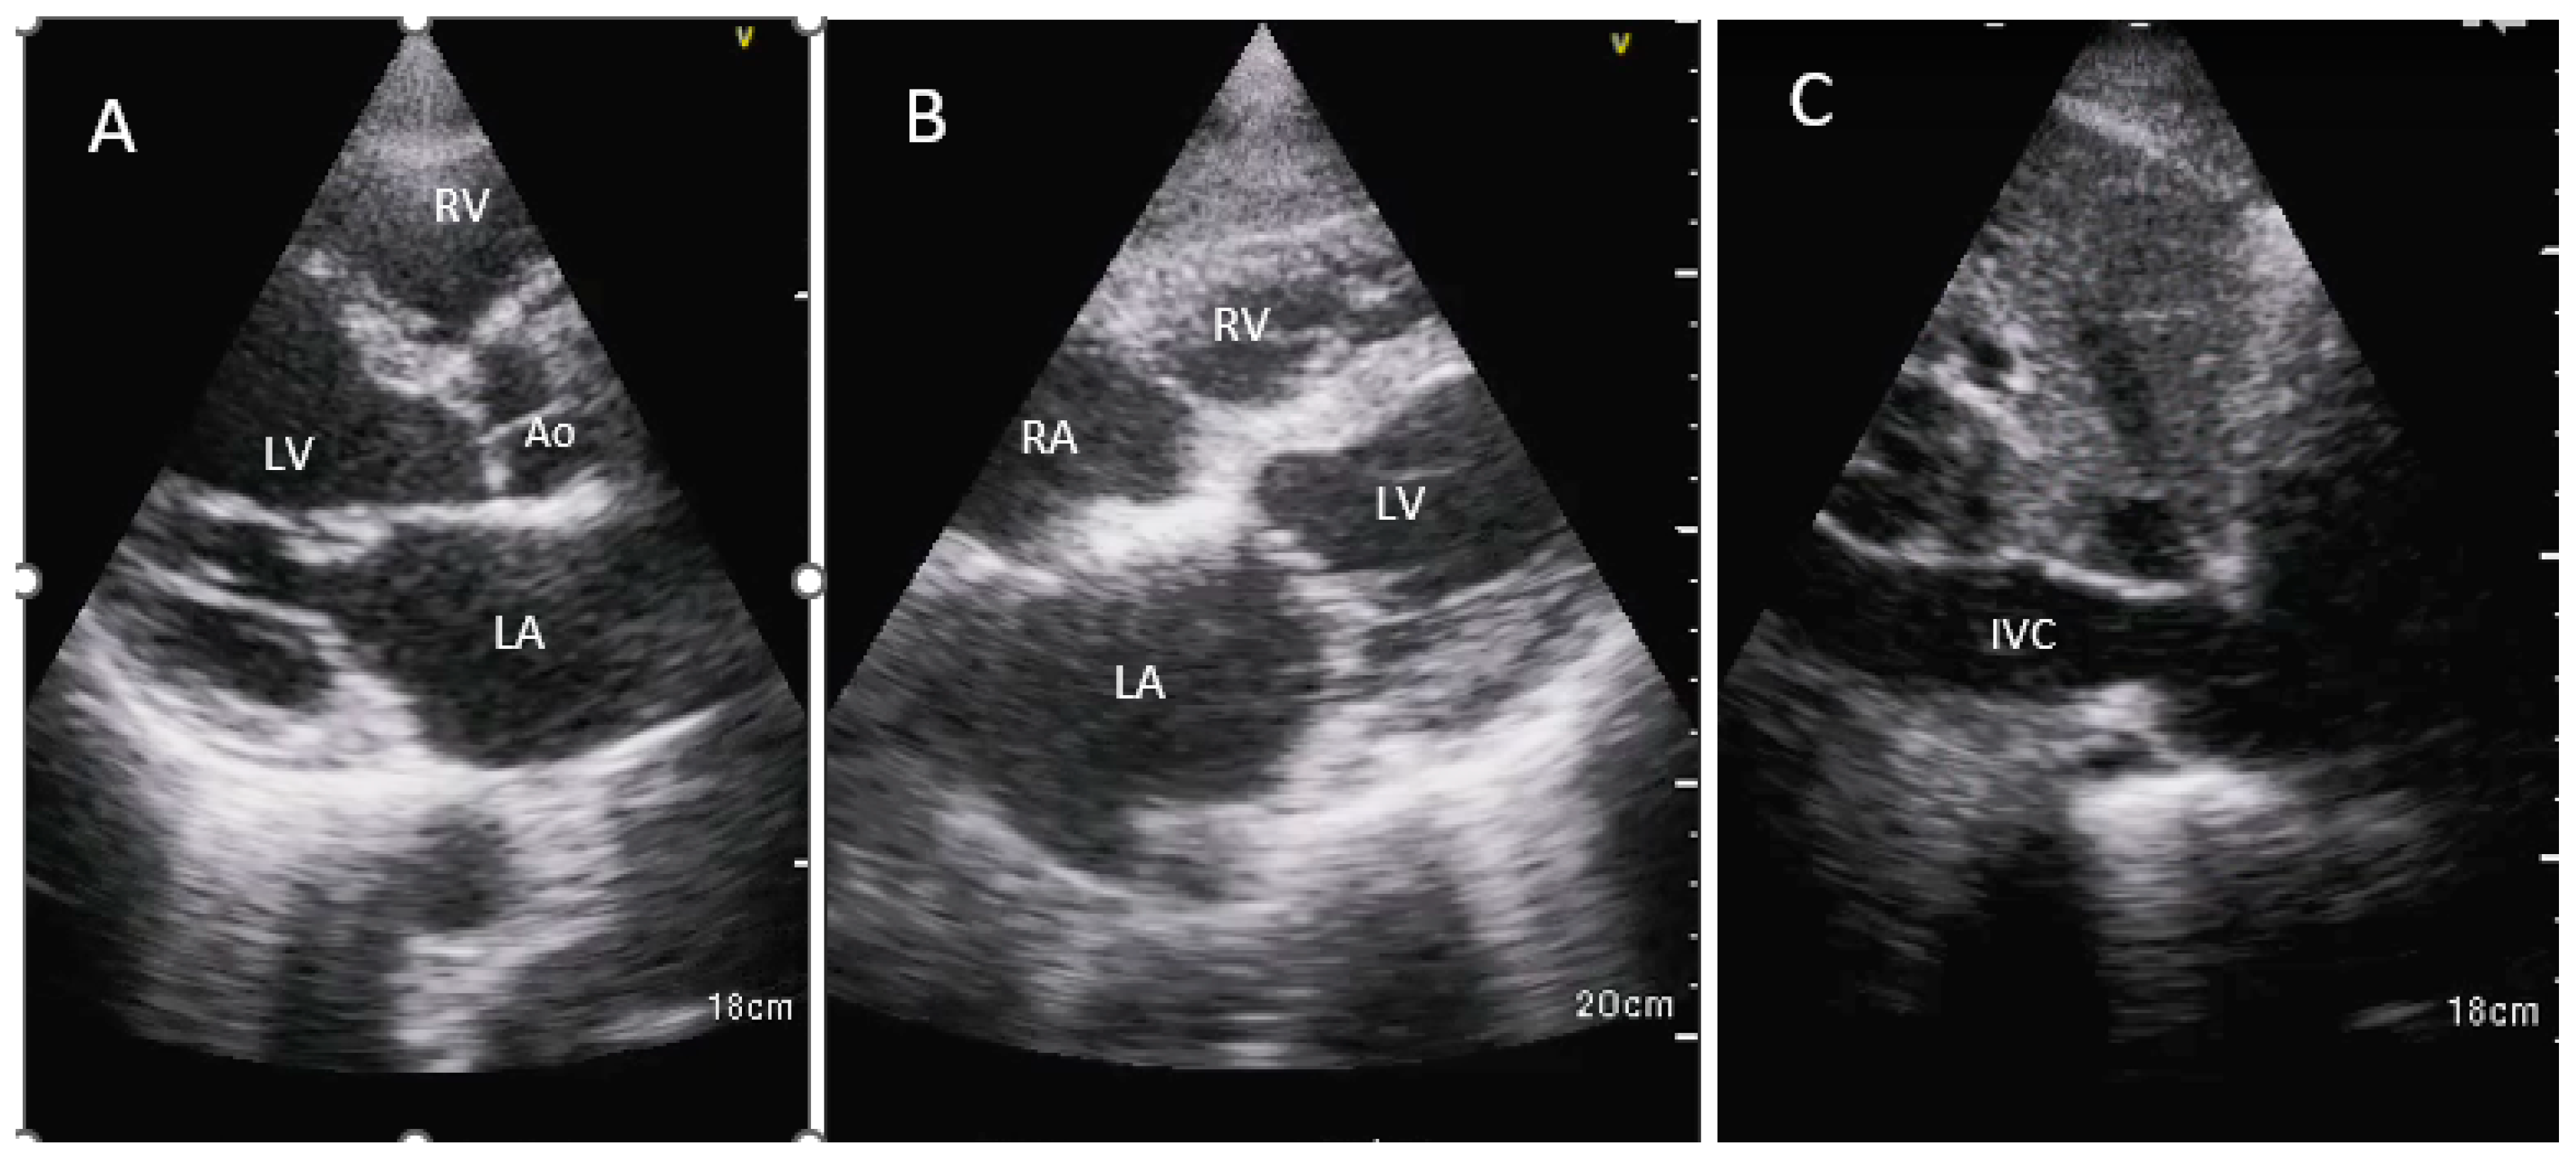

Three views were obtained using two imaging windows: parasternal long axis view, subcostal 4-chamber view and IVC long axis view (Figure 1).

Figure 1. HHE images are shown in the parasternal long axis view (A), subcostal 4 chamber view in the orthogonal plane (B) and inferior vena cava in the sagittal plane (C). Ao, aortic root; IVC, inferior vena cava; LA, left atrium; LV, left ventricle; RA, right atrium; RV, right ventricle.